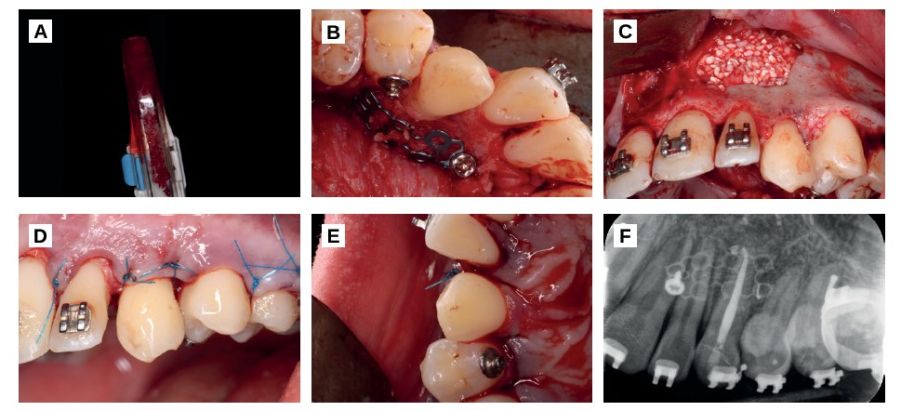

After a follow-up of 12 months, the brackets were removed. The patient was asymptomatic and the canine did not feel mobility or any pathology signs to clinical and radiographic examination (Figures 4A, 4B, 4C). Finally a crown elongation was performed to level the gingival margin to the contralateral canine. A guided surgery splint was planned, based on a previous digital waxing, which marked the position of both the new gingival margin and the bone level (Figures 4D, 4E, 4F).

Once the gum is stabilized, the aesthetic result will be improved with a composite veneer.